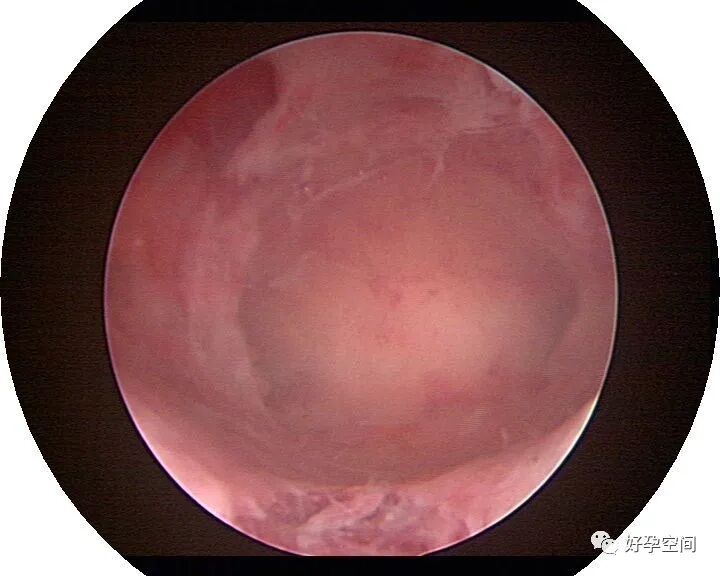

病例18:宫腔粘连变形狭窄